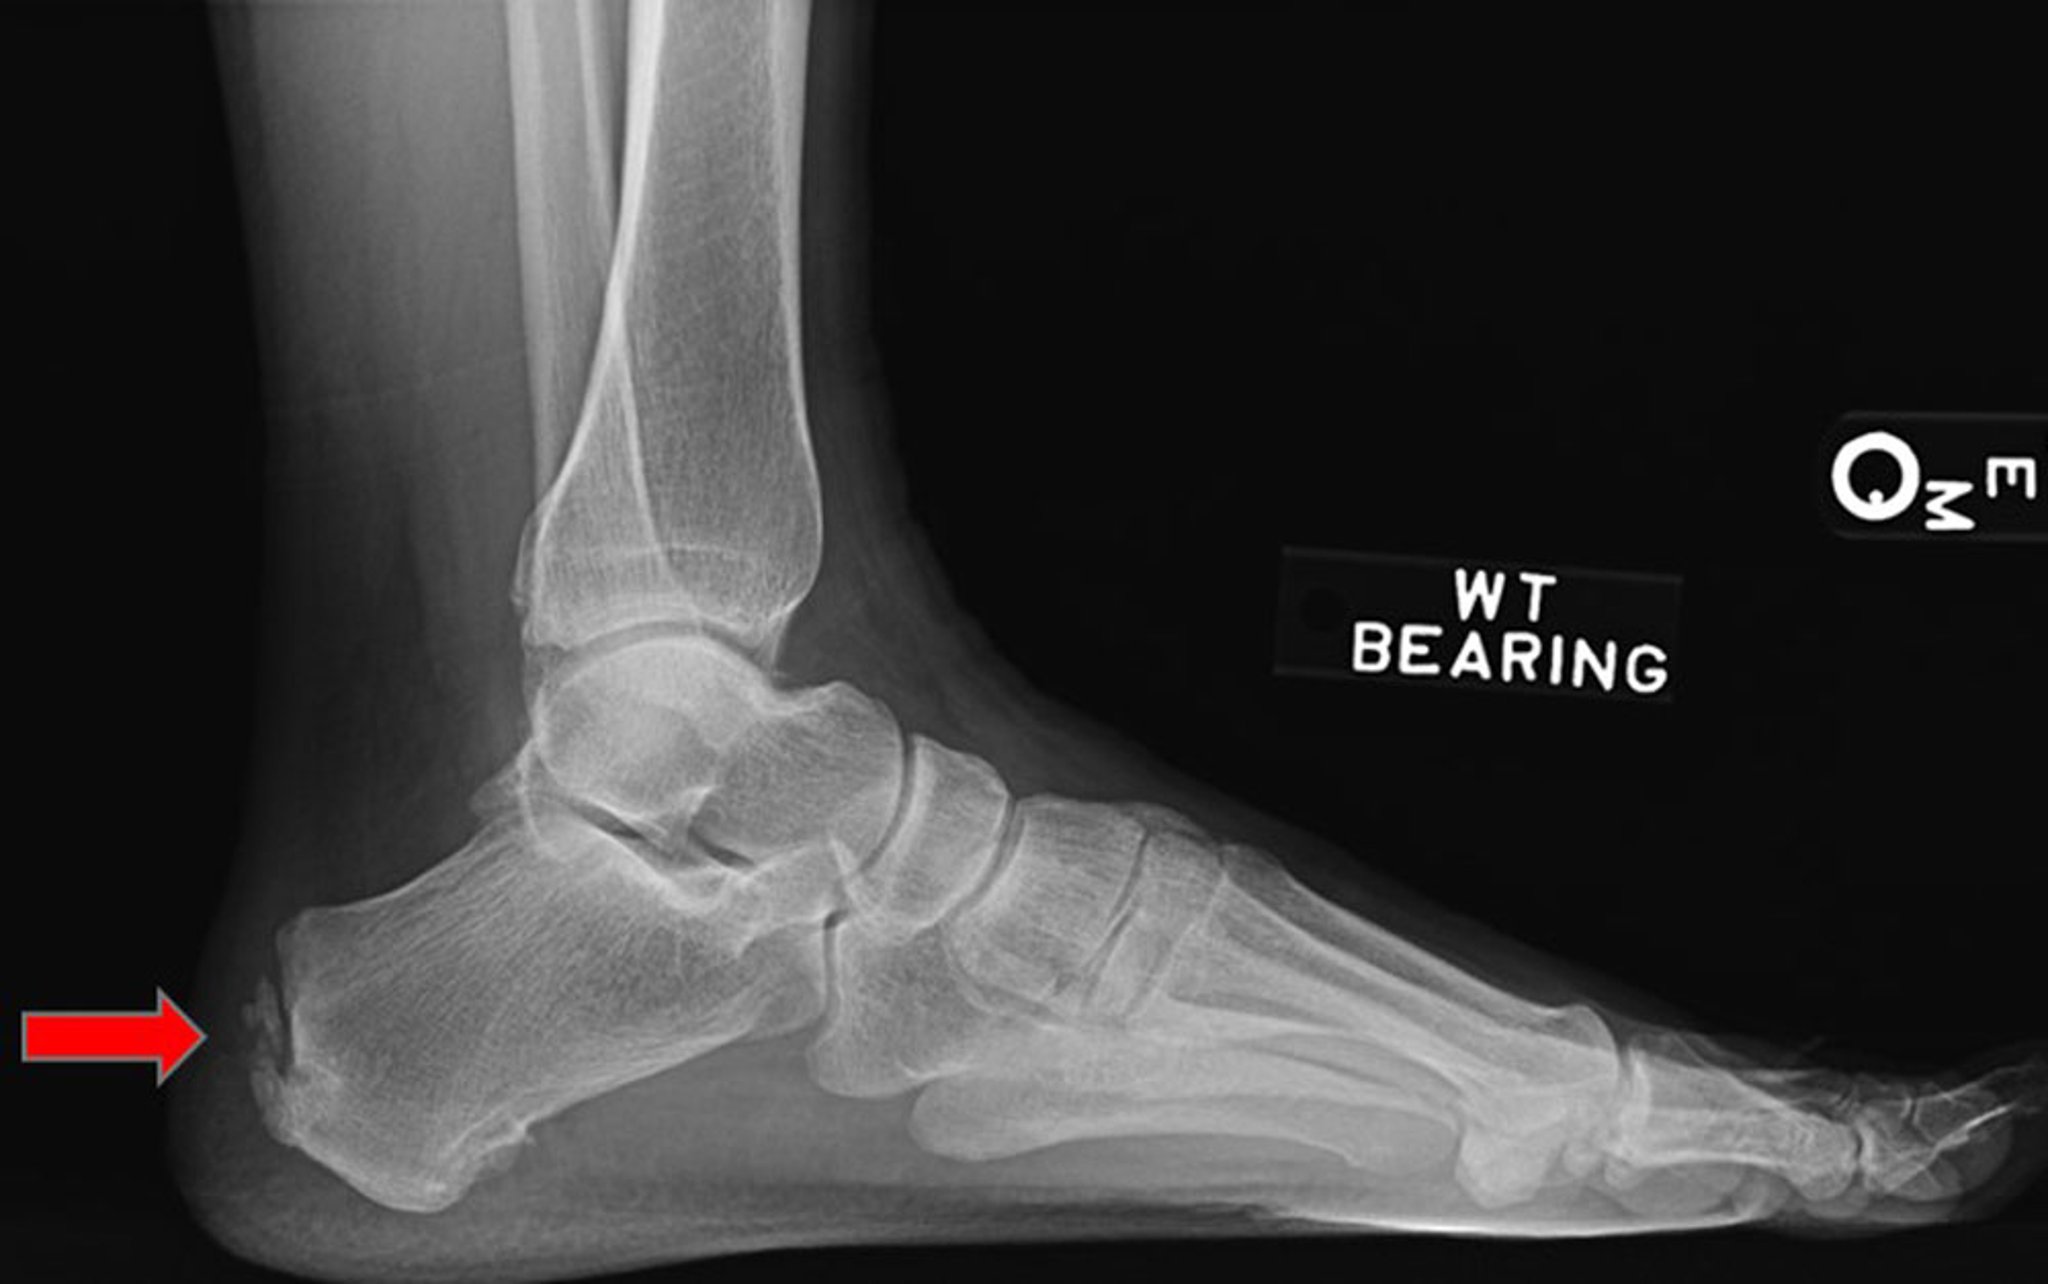

Esta radiografia lateral mostra entesopatia do tendão do calcâneo (seta).

Imagem cedida por cortesia de James C. Connors, DPM.